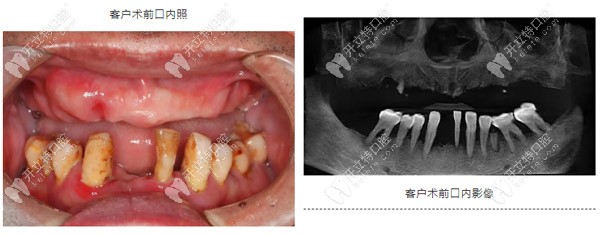

67歲,男,重度牙周炎二十多年,缺失牙十多年,一直戴活動(dòng)義齒,但因?yàn)榱x齒的固位不太好,使用不方便。

希望可以通過(guò)當(dāng)天種牙當(dāng)天帶牙冠的方式恢復(fù)口腔的咀嚼能力,改善生活的質(zhì)量。

重度牙周炎導(dǎo)致上頜牙齒缺失

1、牙齒有重度牙周炎,造成了牙槽骨的重度流失;

2、前牙區(qū)牙槽骨寬度不夠,骨量狹窄;

3、后牙區(qū)骨高度不足,需要進(jìn)行斜型種植;

4、上頜竇腔偏斜,特別考驗(yàn)種植體的位置精準(zhǔn)度,方向需要與竇腔平行;

5、上唇豐滿度不夠,需要進(jìn)行前牙植骨